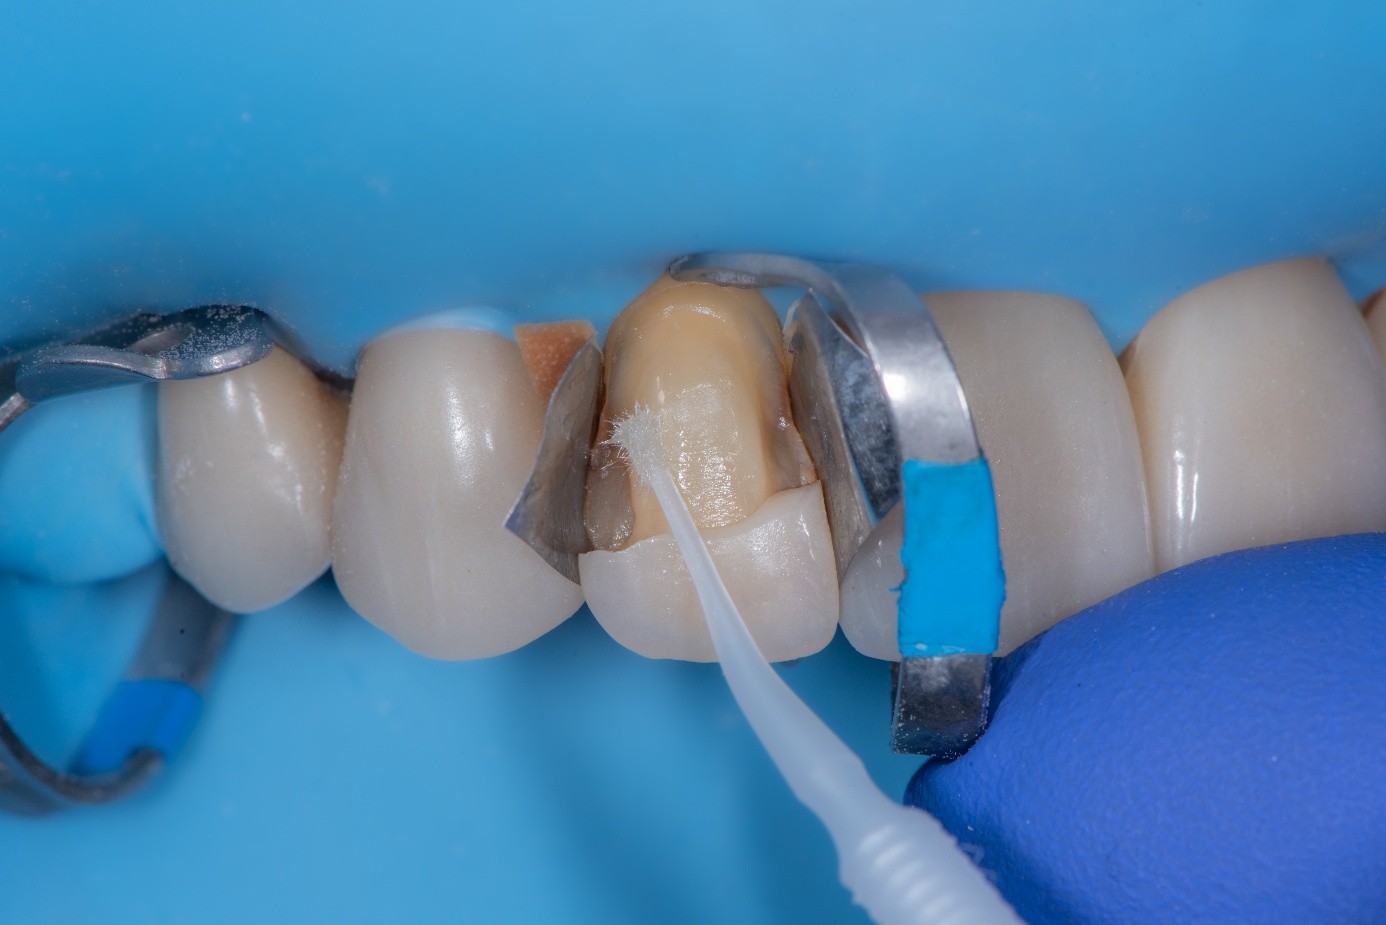

After achieving rubber dam isolation, the fractured composite segment was first air-abraded with aluminum oxide particles to clean and roughen the surface. It was then etched with phosphoric acid for 60 seconds, rinsed, dried, and treated with silane to enhance chemical adhesion (Figure 18 through Figure 20).8,9

The tooth surface was similarly air-abraded to remove biofilm and aged resin remnants, then selectively etched with phosphoric acid. Silane was applied intraorally to the exposed composite surface to promote bonding between the old and new composite layers.10 Following this, a universal bonding agent was applied to both the tooth surface and the fractured composite segment (Figure 21 through Figure 24).

(21.) Intraoral view after rubber dam isolation, showing prepared surfaces: both sandblasted and etched, with silanization applied only to the composite surface, ready for reattachment.

Figure 21

(22.) Intraoral view after rubber dam isolation, showing prepared surfaces: both sandblasted and etched, with silanization applied only to the composite surface, ready for reattachment.

Figure 22

(23.) Intraoral view after rubber dam isolation, showing prepared surfaces: both sandblasted and etched, with silanization applied only to the composite surface, ready for reattachment.

Figure 23

(24.) Intraoral view after rubber dam isolation, showing prepared surfaces: both sandblasted and etched, with silanization applied only to the composite surface, ready for reattachment.

Figure 24